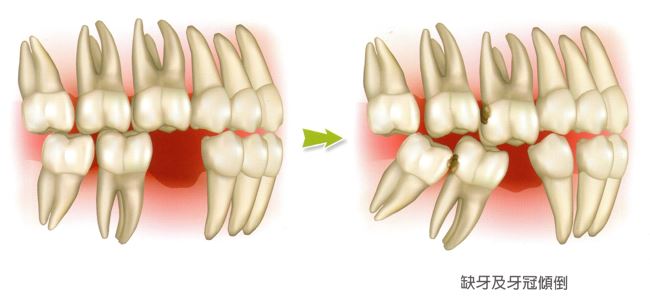

口腔缺牙的問題:

缺牙的後遺症:蛀牙、鄰牙傾斜、咬合不正(如下方x光片所標示)